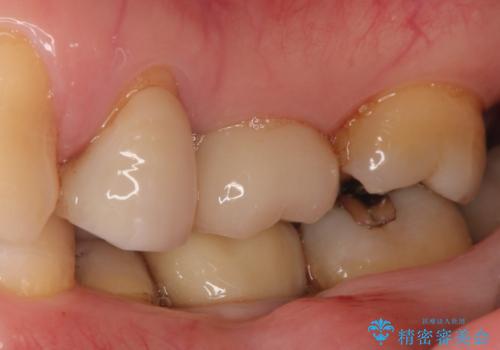

メタルインレーの下は。クラックラインを認めた歯。

- 定期検診にて、奥歯にクラックラインを認めました。

放置すると、抜歯になる可能性も高いため早めの治療を提案し、クラウンにて修復治療を行なっております。

術前説明にてクラックラインを認めることや治療の選択肢及び予後について理解していただいた上で、保存を希望されております。歯髄症状が出なかったため抜髄はせずに治療を完了しております。